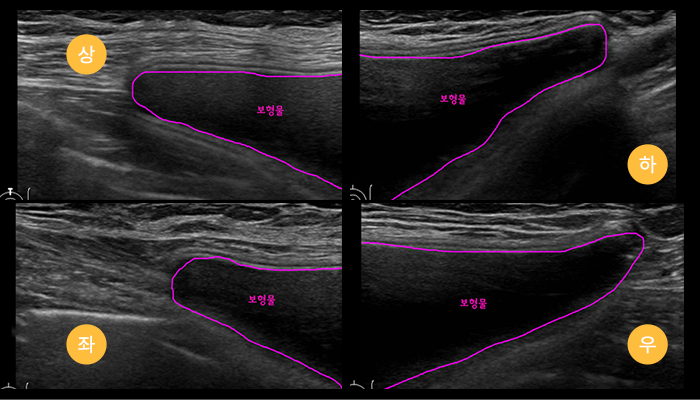

Pre- and Post- Surgery Breast Examination

With breast disease specialists and radiology

experts, we perform precise diagnostics through

mammography, breast ultrasound, and

Mammotome procedures. This one-stop system

ensures thorough evaluation of breast health

and implant condition before and after surgery.

Post-Surgery Implant Assessment

We confirm whether the implants are properly positioned

and monitor for complications such as capsular

contracture, rupture, rippling, or seroma through follow-up

assessments.

Before surgery, every patient undergoes a thorough breast examination using advanced 3D imaging and ultrasound diagnostics to ensure safety and the most accurate surgical planning.